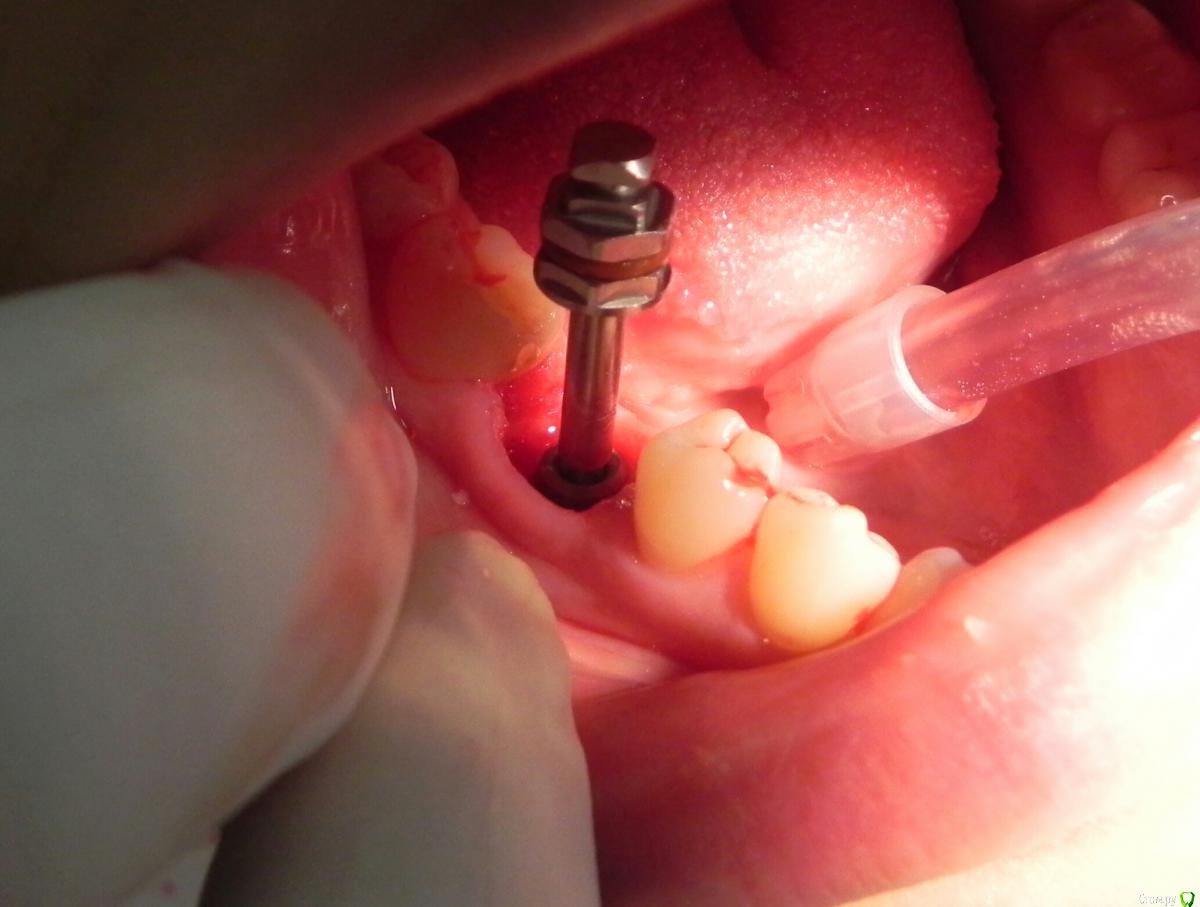

Kostoprav Опубликовано 24 мая, 2016 Поделиться Опубликовано 24 мая, 2016 удалил, вкрутил,графт gen oss, фдм.P.S. сори за плагиат) 3 Ссылка на комментарий